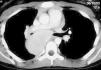

Niña de 12 años, sin antecedentes personales de interés que acudió a nuestro servicio de urgencias refiriendo cuadro catarral con tos escasamente productiva de 15 días de evolución. La exploración física mostró como único hallazgo una hipofonesis en hemitórax izquierdo. El estudio con radiografía simple puso de manifiesto una masa en el mediastino medio y posterior. En la TC se observaba una gran masa localizada en mediastino medio y posterior que captaba contraste de forma homogénea y que comprimía el bronquio principal derecho (fig. 1). La prueba de la tuberculina resultó negativa. El aspirado de médula ósea puso de manifiesto una celularidad normal y los marcadores tumorales analíticos (enolasa, catecolaminas, β -gonadotropina coriónica humana [β -HCG]) fueron negativos. Ante la sospecha diagnóstica de enfermedad de Castleman se realizó un estudio angiográfico de la lesión, que puso de manifiesto una masa hipervascularizada a expensas de un tronco intercostobronquial derecho y una arteria bronquial anómala con origen en tronco tirocervical derecho que pudieron ser embolizados sin complicaciones (fig. 2). Se practicó una resección completa de la masa por toracotomía posterolateral derecha. El estudio macroscópico de la pieza quirúrgica reveló una masa de superficie lisa y parcialmente cubierta por una membrana elástica de coloración blanquecina (fig. 3). Los hallazgos microscópicos correspondían a un ganglio linfático de estructura conservada, con hiperplasia difusa de centros germinales, que adoptaban un patrón "en bulbo de cebolla", la mayoría de ellos con hialinización en relación a la permeación por vasos finos y delicados (figs. 4 y 5). Inmunofenotípicamente se descartó la enfermedad de Hodgkin. Se diagnosticó de enfermedad de Castleman: hiperplasia angiofolicular linfoide variedad hialinovascular.

Figura 1.TC torácica: masa localizada en mediastino medio y posterior con compresión de bronquio principal derecho.